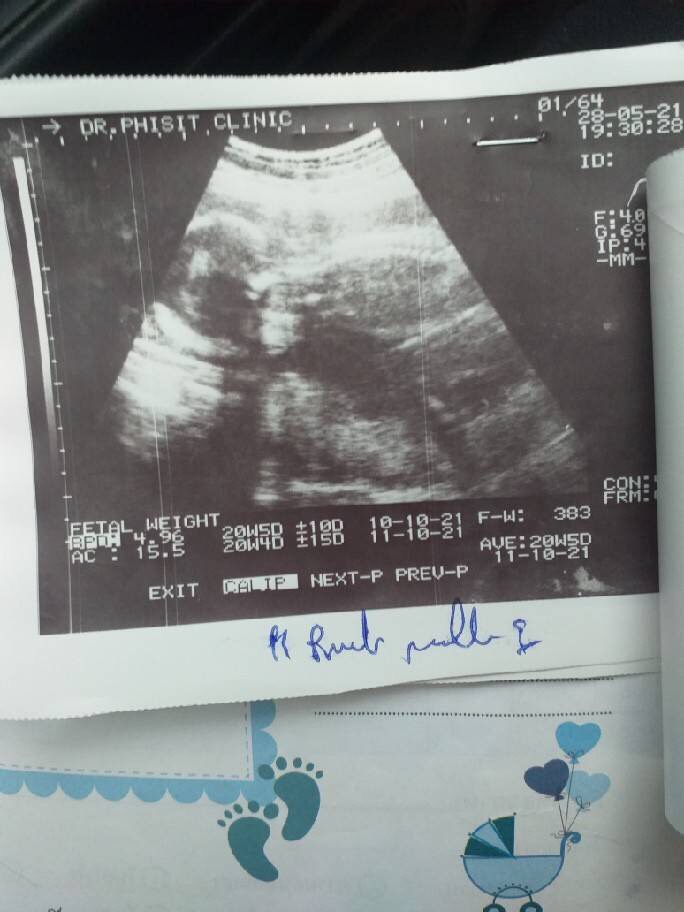

วันที่8ตุลาคม2564 องค์กรLGBT GROUP THAILAND หนุ่มจีสตาร์หรือนายชิษณุพงศ์ไตรรัตน์รักษีประธานองค์กรและเดซี่สมชายเล็กน้อยรองประธานองค์กรเดินหน้าลุยขอความเป็นธรรมให้กับนางสาวสุกฤตาเอียดจะบกอายุ24ปีตั้งครรภ์ได้37สัปดาห์หลังจากที่ฉีดวัคซีนชิโนแวควันที่15กันยายน2564 ที่แหลมทองจังหวัดระยองเวลาประมาณ14.00นหลังจากนั้นเกิดความผิดปรกติเด็กในครรภ์ไม่ดิ้นจึงทำให้สาวตั้งครรภ์รีบเดินทางไปคลีนิคที่ฝากครรภ์ตรวจความผิดปรกติของเด็กในวันเดียวกันกับที่ฉีดวัคซีนผลการตรวจเบื้องต้นเด็กในครรภ์ยังปรกติ

แต่ถัดไปอีกวันคือวันที่16กันยายนสาวตั้งครรภ์ได้เปิดเผยว่าเด็กไม่ดิ้นเลยแต่ก็คงคิดว่าไม่เป็นอะไรเพราะเพิ่งไปตรวจครรภ์มาเมื่อวาน

จนมาถึงวันที่22กันยายนเริ่มรู้สึกปวดท้องเหมือนจะคลอดลูกเมื่อไปถึงโรงพยาบาลนิคมพัฒนาซ8 ปรากฎว่าเด็กเสียแล้วทางโรงพยาบาลจึงส่งตัวไปที่โรงพยาบาลที่เจ้าทุกข์มีประกันสังคมคือโรงพยาบาลจุฬารัตน์แต่ทางโรงพยาบาลจุฬารัตน์ห้องคลอดไม่พร้อมจึงส่งตัวไปที่โรงพยาบาลระยองทำการเอาเด็กออกในวันที่23กันยายน